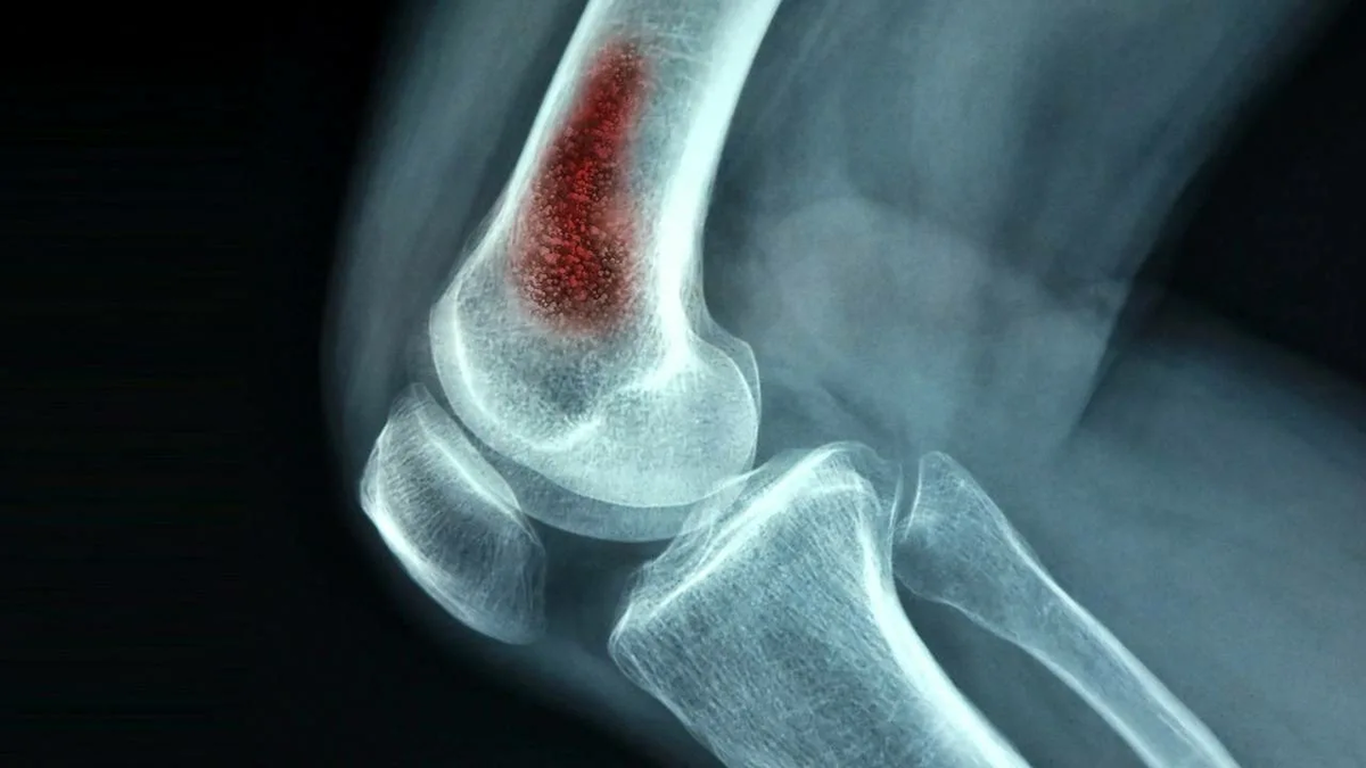

Остеомиелитда суяк тўқимасининг барча элементлари (суяк тўқимаси —остит, кўмиги — миелит, пардаси — периостит ва атроф тўқималар) яллиғланиши кузатилади, — дейди мутахассис. — Хасталик кўпинча одам скелети ғовак суякларининг бўғимга яқин жойида учрайди. Бунга йиринг ҳосил қилувчи микроблар, масалан, стафилококк, стрептококк сабаб бўлади.

Остеомиелит оқибатида суяклар деформацияси, сохта бўғимлар ҳосил бўлиши ҳам амалиётда кузатилади.

Остеомиелитга учраган найсимон суякларда паталогик синиш, суяк тўқимасининг чириши, ўсишдан тўхташи каби ҳолатлар шаклланиши хавфи ҳам мавжуд.